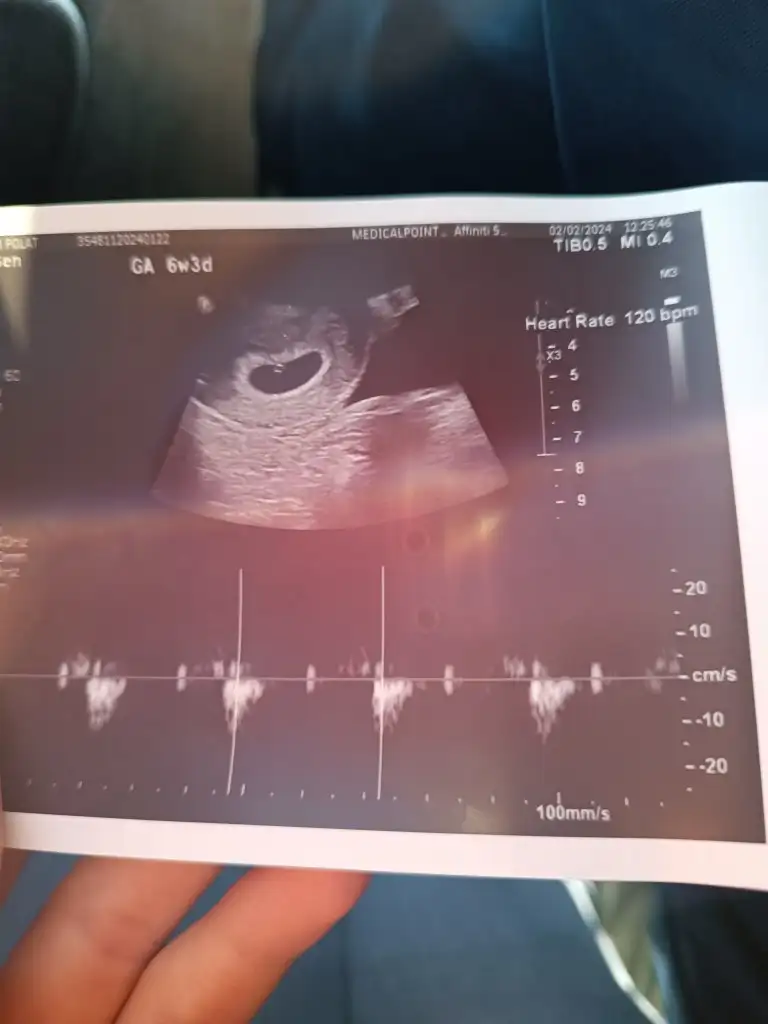

Canım kalp atışı 140 altıya erkek deniyor sana kaç dendiLinakiz normalde 6+4 du ultrason görüntüsüne göre 6+5 haftalık kalp atışını duyduk çok şükür kızlar keseye göre tahmin yapanlariniz varsa bakabilir misiniz

Senin de sanki 120 mi yazıyor bpm denen kalp atışı sayısı demek bana da 114 demişti 2 gün önce canım bakalım tutacak mıLinakiz normalde 6+4 du ultrason görüntüsüne göre 6+5 haftalık kalp atışını duyduk çok şükür kızlar keseye göre tahmin yapanlariniz varsa bakabilir misiniz